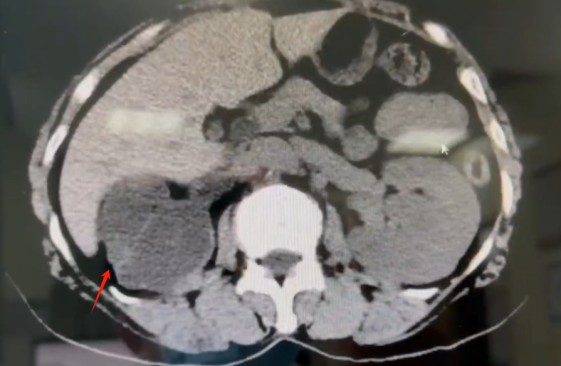

近日,我院泌尿外科团队成功为一位饱受多年右侧腰腹部疼痛困扰的67岁患者(化名:李阿姨),实施了高难度、高精度的腹腔镜下右肾切除术。手术过程顺利,患者恢复良好,术后第4天即康复出院。 李阿姨长期遭受右侧腰腹部的疼痛困扰。来院就诊后,泌尿外科蒋勇军主任详细询问病史得知,她曾因右侧肾结石接受过手术治疗。进一步的系统检查(包括下腹部CT平扫和CT尿路成像)揭示了问题根源:患者右侧肾脏存在严重肾积水,肾实质已极度萎缩、变薄,功能完全丧失。影像学显示,在排泄期长时间观察下,右肾已无显影,确认其功能完全丧失。 蒋主任分析认为,患者既往的结石病史可能导致输尿管狭窄或闭锁,引发了长期的尿路梗阻和肾积水,最终造成右肾不可逆的萎缩。而萎缩肾脏可能存在的炎症,正是其持续疼痛的原因。 面对患者切除无功能病肾的诉求,蒋勇军主任团队经过严谨评估,决定迎难而上,采用腹腔镜微创技术实施右肾切除术。该手术属于最高难度的四级手术,对医院综合实力和主刀医生的技术要求极高。手术面临两大挑战: 1、组织粘连重:萎缩的肾脏因继发炎症,与周围组织形成致密粘连,分离难度大。 2、血管处理难:萎缩肾脏的血管结构不清、纤细且被纤维组织包裹,解剖分离需极其精准,稍有不慎易损伤邻近重要血管和器官。 6月17日,手术如期进行。术中腹腔镜视野下,可见患者右肾萎缩呈“皮囊样”,肾实质薄如纸片,与周围组织粘连紧密,肾血管结构不清。蒋勇军主任团队凭借丰富的腹腔镜操作经验和精湛的解剖技巧,如同精雕细琢般,仔细分离粘连组织,精准处理纤细的肾血管及输尿管,最终完整、安全地切除了病变右肾。手术历时约3小时,顺利完成。 术后病理检查结果证实为“肾萎缩”,与术前诊断完全一致。在泌尿外科医护团队的精心治疗和护理下,李阿姨恢复迅速,疼痛解除,术后第4天即满意出院。出院前,蒋主任特别叮嘱她:务必保护好唯一的左肾,定期复查泌尿系统,发现异常及时就医处理。